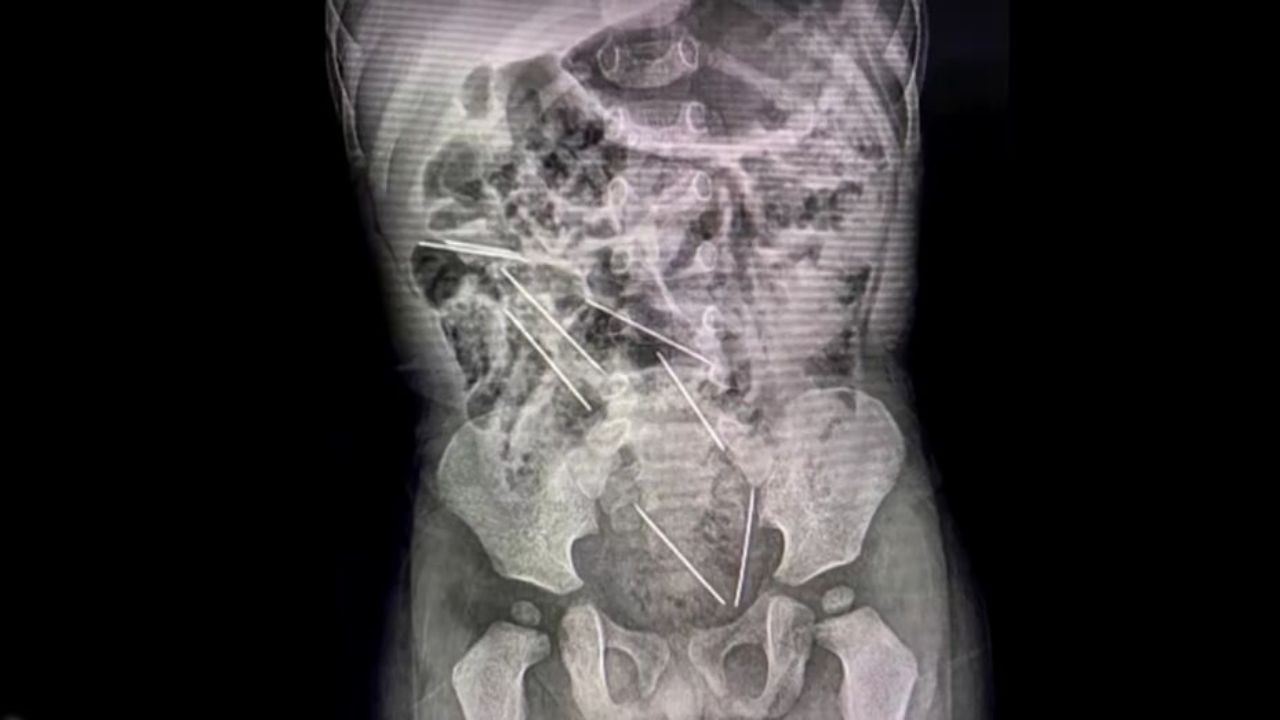

El pequeño ingirió accidentalmente ocho agujas inyectables que la mujer usaba para suministrarle medicamentos a las vacas.

Una ecografía abdominal, reveló las agujas en su interior, siendo intervenido de emergencia.

Los doctores tardaron alrededor de dos horas para retirar todas las agujas, mismas que estaban en diferentes partes del estómago y el tracto intestinal del niño.

Las agujas en el interior del pequeño se ubicaban: dos en el peritoneo lado derecho, tres en el izquierdo, uno en la pared abdominal, uno en la vejiga y la otra en el recto.

Las agujas que estaban en la vejiga y en el recto pusieron la vida del infante en riesgo, según el reporte médico del cirujano pediatra, Efraín Salazar Tito, quien se encargó de manejar la operación.

No obstante, los doctores pudieron extraerlas todas tras abrir el abdomen del niño.